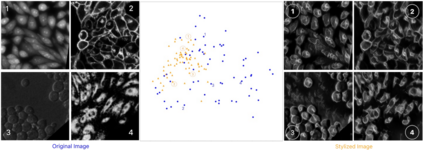

Deep-learning models have been successful in biomedical image segmentation. To generalize for real-world deployment, test-time augmentation (TTA) methods are often used to transform the test image into different versions that are hopefully closer to the training domain. Unfortunately, due to the vast diversity of instance scale and image styles, many augmented test images produce undesirable results, thus lowering the overall performance. This work proposes a new TTA framework, S$^3$-TTA, which selects the suitable image scale and style for each test image based on a transformation consistency metric. In addition, S$^3$-TTA constructs an end-to-end augmentation-segmentation joint-training pipeline to ensure a task-oriented augmentation. On public benchmarks for cell and lung segmentation, S$^3$-TTA demonstrates improvements over the prior art by 3.4% and 1.3%, respectively, by simply augmenting the input data in testing phase.